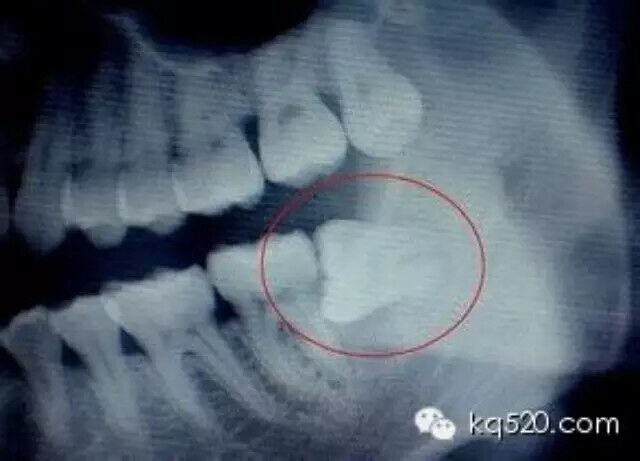

一圖讀懂 l 拔智齒前應(yīng)了解的六個(gè)問(wèn)題....

(轉(zhuǎn)) kq520.com